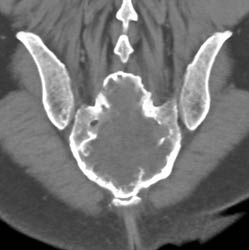

Patellar Fracture